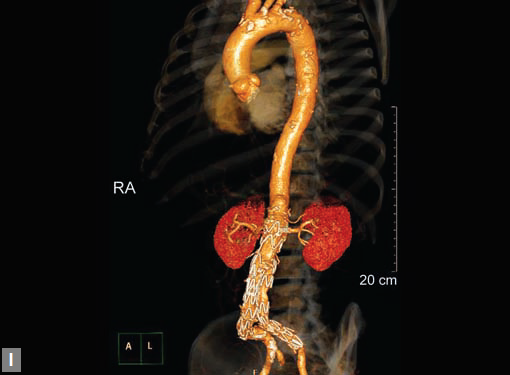

Figs 19A to Y (A to C) Scannogram (A), plain (B) and contrast study (C) show partial anomalous pulmonary venous connection; (D to F) Heterotaxy; (G) Aortic occlusion; (H and I) Aortic stents; (J) Aortic dissection with ‘Benz’ sign due to second dissection within the true lumen; (K, L and M) Aortic dissection with thrombus in pseudolumen following catheter angiogram; (N) Aortic dissection involving common carotid arteries and subclavian artery; (O, P, Q and R) Aortic dissection with right renal artery arising from true lumen and left renal artery from false lumen; (S, T, U and V) Stanford B dissection with extension Y to iliac vessels; (W to Y) Aneurysmal dilation of ascending aorta